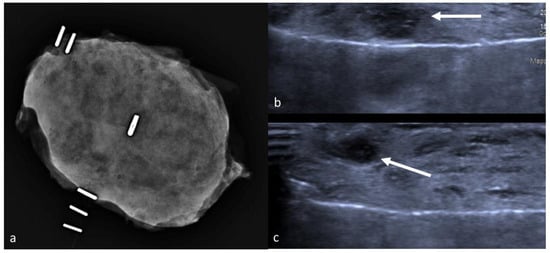

- Colakovic, N.; Zdravkovic, D.; Skuric, Z.; Mrda, D.; Gacic, J.; Ivanovic, N. Intraoperative ultrasound in breast cancer surgery—from localization of non-palpable tumors to objectively measurable excision. World J. Surg. Oncol. 2018, 16, 1–7. [Google Scholar] [CrossRef] [PubMed]

- Haid, A.; Knauer, M.; Dunzinger, S.; Jasarevic, Z.; Köberle-Wührer, R.; Schuster, A.; Toeppker, M.; Haid, B.; Wenzl, E.; Offner, F. Intra-operative sonography: A valuable aid during breast-conserving surgery for occult breast cancer. Ann. Surg. Oncol. 2007, 14, 3090–3101. [Google Scholar] [CrossRef] [PubMed]

- Fortunato, L.; Penteriani, R.; Farina, M.; Vitelli, C.E.; Piro, F. Intraoperative ultrasound is an effective and preferable technique to localize non-palpable breast tumors. Eur. J. Surg. Oncol. (EJSO) 2008, 34, 1289–1292. [Google Scholar] [CrossRef]

- Ramos, M.; Díaz, J.C.; Ramos, T.; Ruano, R.; Aparicio, M.; Sancho, M.; González-Orús, J.M. Ultrasound-Guided Excision Combined with Intraoperative Assessment of Gross Macroscopic Margins Decreases the Rate of Reoperations for Non-Palpable Invasive Breast Cancer. Breast 2012, 22, 520–524. Available online: https://www.unboundmedicine.com/medline/citation/23110817/Ultrasound_guided_excision_combined_with_intraoperative_assessment_of_gross_macroscopic_margins_decreases_the_rate_of_reoperations_for_non_palpable_invasive_breast_cancer_ (accessed on 30 October 2020). [CrossRef]